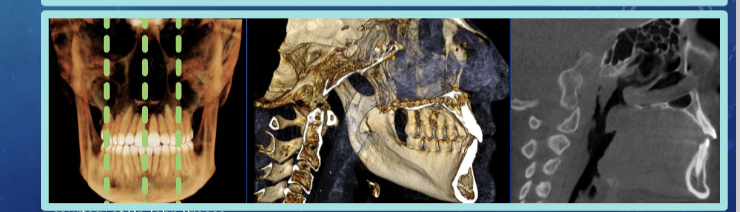

CBCT scan - cone beam, computed tomography

cone-shaped x-ray beam, rotates around the patients head

spatial res - voxels 3-dimensional pixels

Coronal plane

axial plane

sagittal plane

anatomical/ orthogonal projections

multiplanar reconstruction/ reformation

volumetric rendering